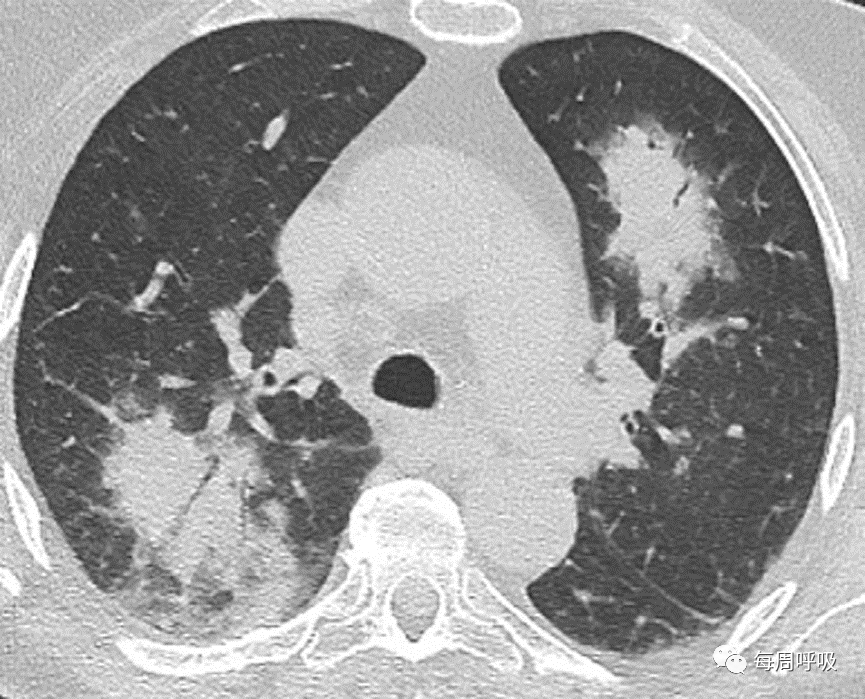

GGO(单独或呈铺路石状)是OP的另一常见胸部CT表现。同样,对于此类表现,需要进行广泛的鉴别诊断。鉴别诊断包括肺泡蛋白沉积症,感染(如耶氏肺孢子菌肺炎),结节病,外源性脂质性肺炎,粘液腺癌,以及呋喃妥因诱导的OP。就目前的相关性而言,COVID-19的典型外观与OP的外观有显著重叠(图27)。与电子烟或电子烟产品使用相关的肺损伤是另一个患病率不断上升的疾病,其结果可能与OP的结果相同(图28)

图27 COVID-19和机化性肺炎(OP)。一名55岁男性确诊COVID-19, CT表现典型。肺中部(A)和肺下段(B)的CT平扫图像显示右肺上叶磨玻璃影(GGO)伴小叶内间隔增厚,各肺下叶周边均有GGO和实变影,左肺下叶为小叶周围型。这些表现也是典型的OP。